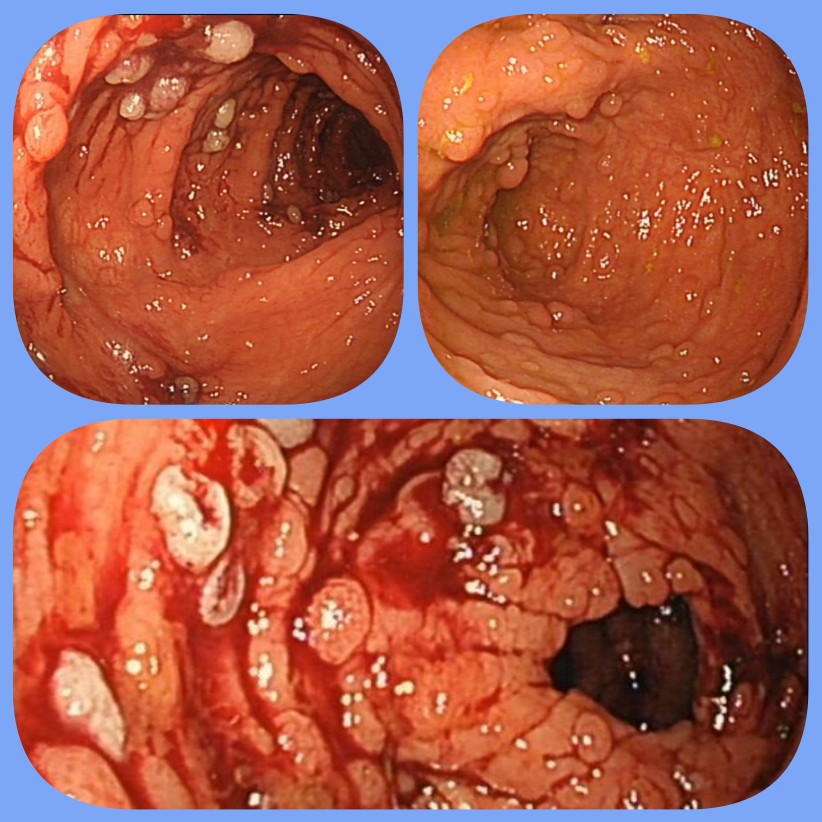

肠内密布息肉恍如“溶洞”,摘除多达200余枚

近日,南京市中西医结合医院内窥镜中心收治了一位患有肠息肉的中年男性患者。与很多肠息肉患者不同的是,这位患者被确诊为“家族性腺瘤性息肉病”。肠镜下发现他的全结肠密布0.5-2.0cm大小不等的各类息肉,数量粗略估算有几百枚。如果手术的话,难度很大,如果不手术的话,放任不管可能有诱发癌变的风险。

内窥镜中心陈昱倩主任专门请该中心特聘专家、江苏省人民医院消化科副主任李学良主任医师亲自为其手术,两位专家为其顺利完成了内镜下多发性息肉摘除手术。手术长达3小时,其中光摘除息肉就用了两个多小时,前后共摘除200余枚息肉,整个手术过程很顺利,患者术后恢复较好,72小时后顺利出院。